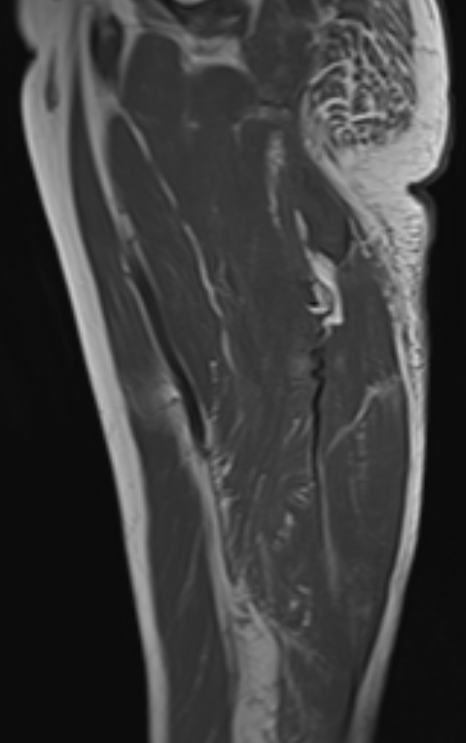

Corrugated tendon sign - torn retracted hamstring